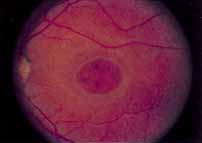

During the early stage of the dystrophy, when patients demonstrate a slight-to-moderate decrease in visual acuity and minimal color defects, there are minor or no visible fundus abnormalities. At most, the foveal reflex may be absent and there may be some increased granularity of the retinal pigment epithelium in the macula. Later, there is a decrease of visual acuity to the 20/400 range, oval atrophy of the macular retinal pigment epithelium (“beaten bronze” atrophy), and associated choroidal atrophy (Fig. 3). A characteristic bull's-eye maculopathy, similar to that seen in patients with chloroquine retinopathy, may also be seen.90 Photophobia, occasional nyctalopia, incomplete-to-complete color defects, and a central scotoma are often present. The symmetry of the process in both eyes is remarkable.

Ancillary Tests

Fluorescein angiography demonstrates increased transmission of choroidal fluorescence in the macula during early phases of the study, without late leakage of dye or fluorescein staining. In addition, an annular pattern of hyperfluorescence is often seen in the macula, highlighting the bull's-eye pattern seen on fundus examination (Fig. 4). Visual field defects include central scotoma, peripheral field loss, and ring scotoma.